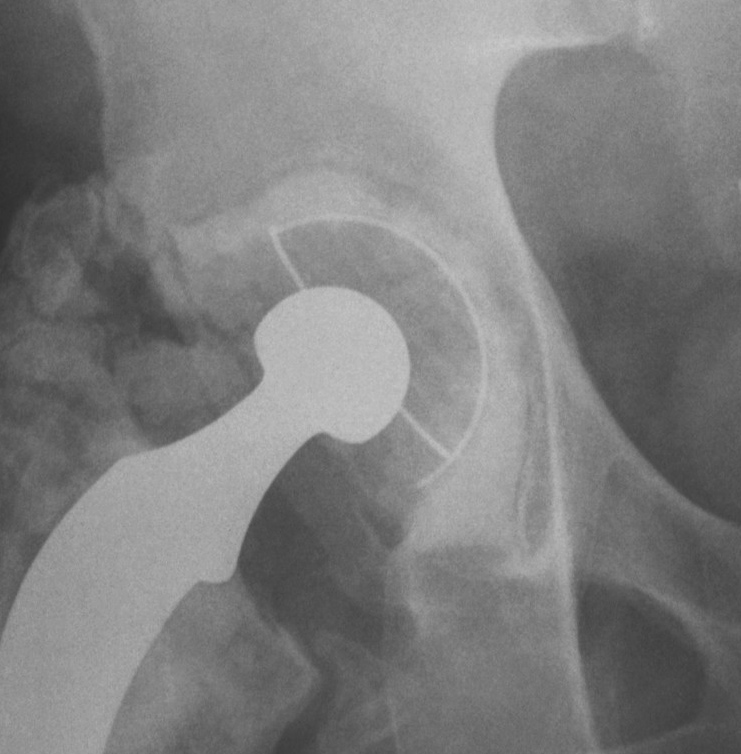

Paprosky Classification

Based on ability of the remaining host bone

- to provide initial stability to a hemispherical cementless acetabular component

- until ingrowth occurs

Type 1

Undistorted rim

- anterior and posterior columns intact

- no superior migration

- may have some contained deformities

- ishium, teardrop and Kohlers line intact

Type 2

Distorted but intact rim

- can support a hemispherical cementless implant

Some distortion, minimal superior migration

- at least 50% good support by host bone

- anterior and posterior columns intact

- no substantial osteolysis of ischium or teardrop

2A

- superomedial migration but superior rim intact

2B

- < 1/3 superior deficit

- remainder is still supportive

- replace with allograft for bone stock

2C

- medial migration to Kohlers, but wall intact

- rim is supportive

- manage as for protrusio

Type 3

Non supportive rim

- columns not supportive, superior migration> 3 cm

- require structural allograft for support